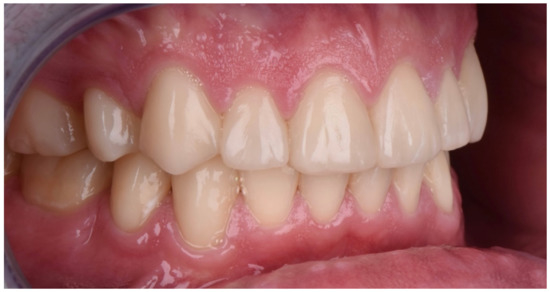

2. Clinical Report

2.1. Planning Phase

2.2. Restorative Phase